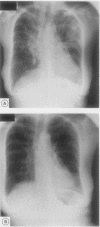

BACKGROUND: Low dose methotrexate has become established in the treatment of refractory rheumatoid arthritis. Until recently it has been considered that the use of a low dose regimen (< 20 mg/week) would avoid the pulmonary toxicity associated with the higher doses prescribed in malignant disease. Although initial experience with low dose methotrexate was encouraging, an increasing number of cases of an acute, life threatening pneumonitis are being reported in patients with refractory rheumatoid arthritis. PATIENTS: Since 1984 43 patients with refractory rheumatoid arthritis have been established on low dose methotrexate in the Oxford Health District. Five of these patients have subsequently developed acute methotrexate induced pneumonitis. The clinical and radiological features of these cases are described and previous reports reviewed. RESULTS: Five patients having low dose methotrexate treatment developed acute pneumonitis. Presentation was subacute and dominated by constitutional features. Respiratory symptoms developed insidiously but progressed rapidly with increasing dyspnoea associated with severe hypoxia. Chest radiographs were non-specific, showing diffuse interstitial infiltration and alveolar shadowing. Microbiological investigation gave negative results. In all cases methotrexate was discontinued and high dose corticosteroids started, with rapid clinical and radiological improvement. After withdrawal of steroid both clinical and radiological resolution was maintained at follow up. CONCLUSION: Acute pneumonitis is an uncommon but serious adverse effect of low dose methotrexate treatment for refractory rheumatoid arthritis. The initial presentation is non-specific and a high index of suspicion is required as respiratory failure may develop rapidly. Management depends on exclusion of infection, withdrawal of methotrexate, and high dose corticosteroid treatment. Full supportive treatment is indicated as the prognosis in such patients is good.